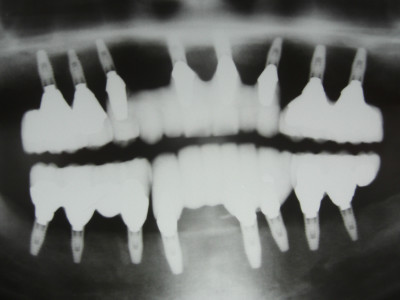

最終補綴物セット

この患者様は総入れ歯が合わなく苦しんでおられました。

まだ50代後半の方で総入れ歯から何とか脱却したいという事で、フルマウスインプラント治療を選択されました。

大変良く噛み込めますと、喜んでいただきました。